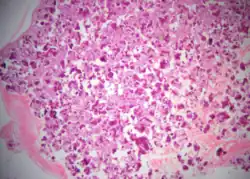

Cemento-ossifying fibroma is a well-demarcated lesion, often encapsulated by a thin fibrous capsule and sharply separated from adjacent normal bone. It shows significant internal variation, with differing amounts of fibrous and mineralized tissue—even within the same lesion. Mineralization is often more prominent centrally and typically includes osteoid, woven to lamellar bone, and dense basophilic cementum-like calcifications. Bony trabeculae may fuse into broad sheets or form thick, anastomosing strands. Osteoblastic rimming is commonly seen around bone trabeculae.[27]

The stroma is fibroblastic and may exhibit areas of hypercellularity and nuclear hyperchromasia; however, mitotic activity is rare and cellular atypia is minimal .[28] The mineralized component may include acellular or paucicellular cementum-like spheres along with bone structures .[28]

Though rare, hemorrhagic cystic degeneration—resembling aneurysmal bone cyst formation—can occur, more commonly in juvenile variants.[27][29] Histological overlap can exist among subtypes: psammomatoid and trabecular JOF may exhibit features resembling COF, and vice versa. In syndromic cases, such as gnathodiaphyseal dysplasia, COF lesions appear more fibrous with basophilic, acellular bone droplets and spherical ossicles, but histologically resemble nonsyndromic counterparts .[30]

Histologically, COF comprises a fibrocellular stroma with varying degrees of ossification, including trabecular or lamellar bone and cementum-like material.[35] Differentiation from other fibro-osseous lesions—such as fibrous dysplasia and cemento-ossifying fibroma—requires histopathological assessment.[36]